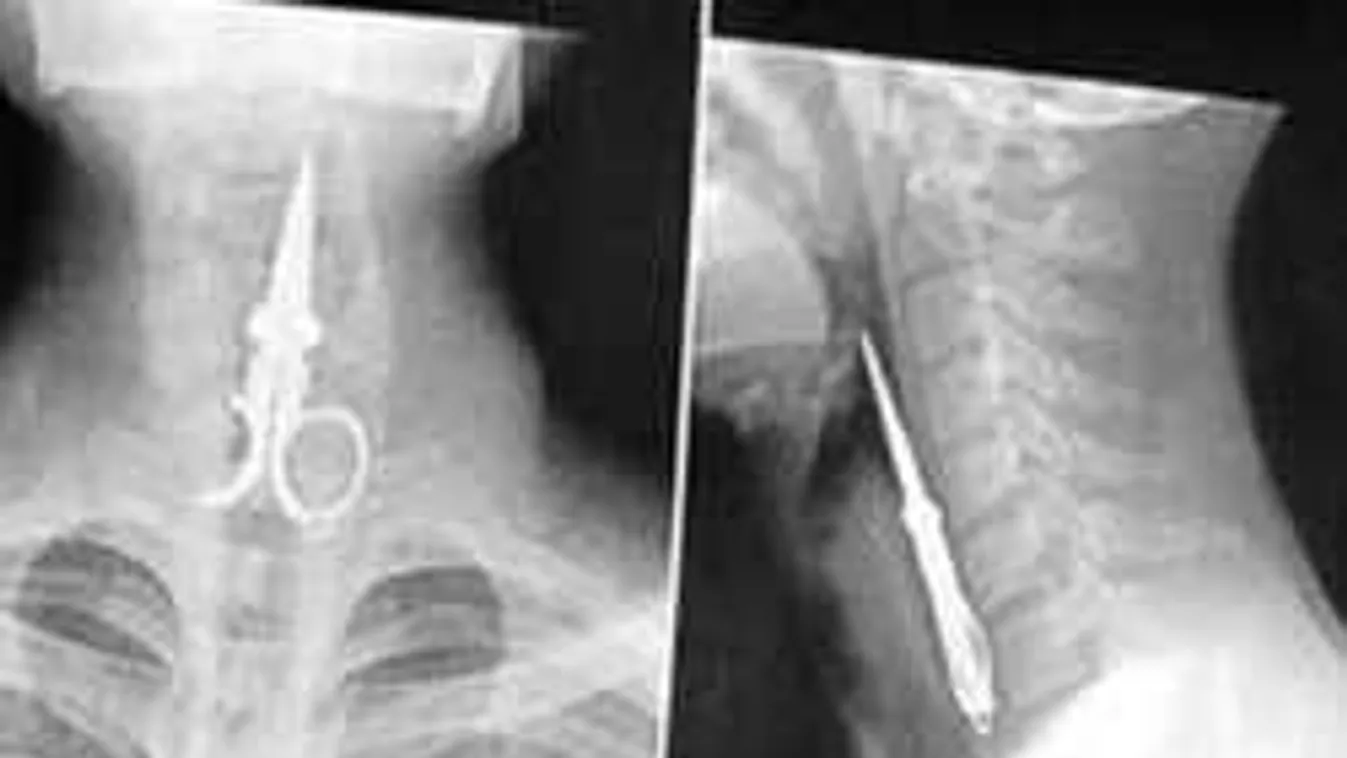

3. Kisolló

![]()

Soha, soha, de soha ne használja fogpiszkáló helyett kisollót, különben ez lehet a vége. Sajnos nem tudjuk, hogy mi lett a végeredmény, de reméljük, hogy a beteg túlélte.